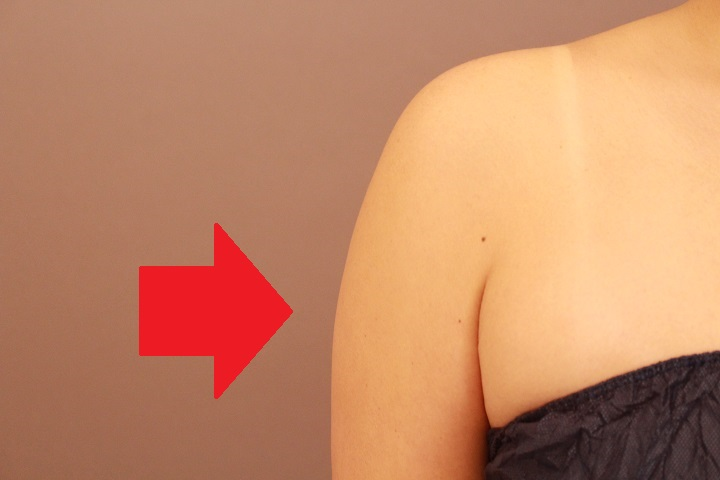

二の腕の脂肪吸引 まとめ

今日は二の腕・肩の脂肪吸引の症例をまとめます。 この手術で皆さんが一番喜ぶ変化はこの赤い矢印で刺している横の出っ張りの変化で...